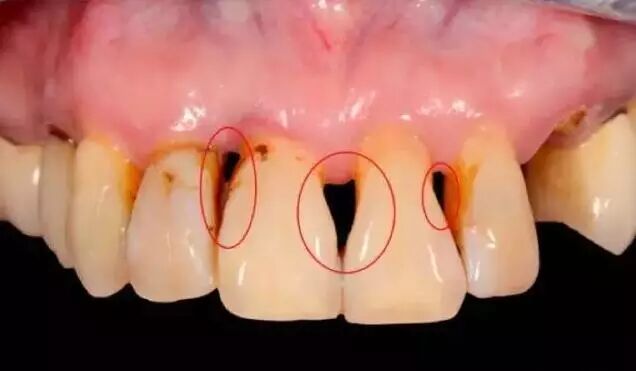

牙周病

如果牙龈红肿,刷牙、用牙线时出血,有口臭——这是牙龈炎!亲爱的别急,这时候还有得救,经过认真刷牙、使用牙线和洗牙等相应治疗是可以恢复的。

但是!如果发现上面的症状加重,同时还有牙龈萎缩,牙齿之间出现缝隙,牙齿松动,牙齿脱离——这是牙周病!得治!